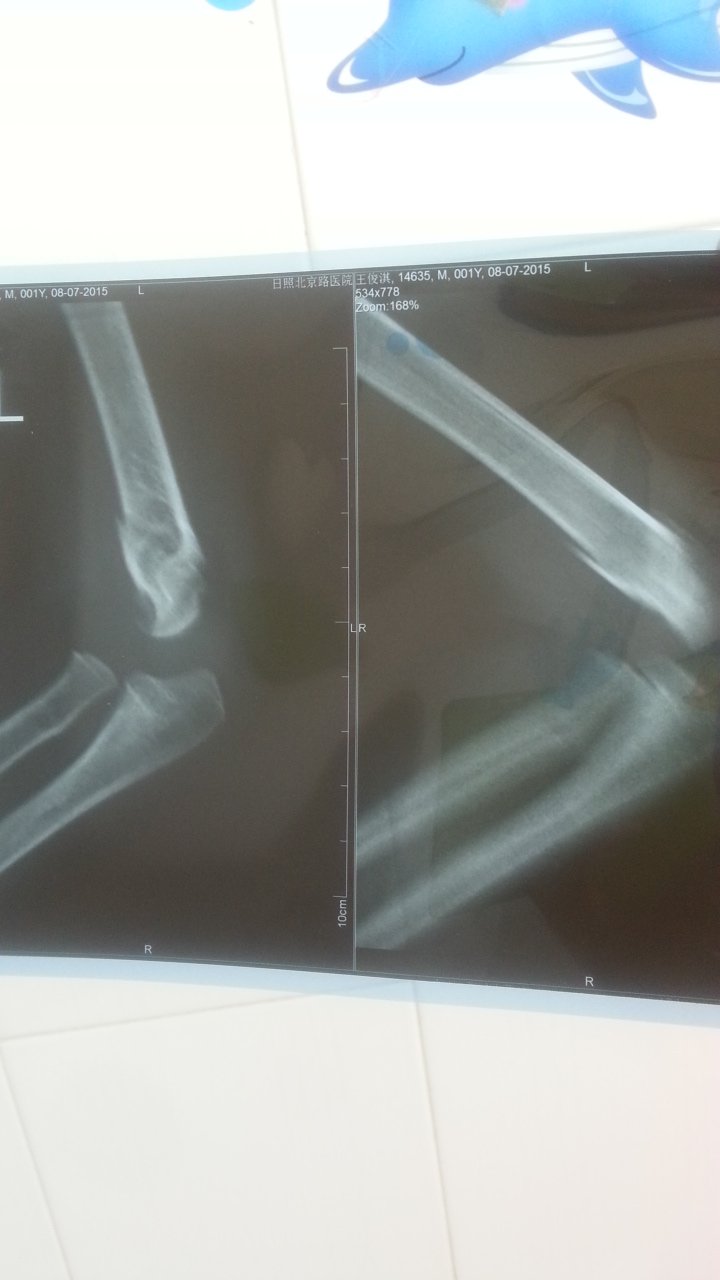

两岁宝宝摔倒后肱骨远段髁上骨折,已经一周了,没给他打石膏,只是绷带固定的,这样行吗? 点击展开 匿名用户 2015-07-08 14:29 满意回答 你好,病情分析,2岁,肱骨远编挡段髁上骨折,无恨局炼明显分离及错位,考虑用绷带固定可唉脂以 cn#BppakBVVfa 2015-07-08 14:34 宝宝知道提示您:回答为网友贡献,仅供参考。 相关问题 8岁小孩左手肱骨髁上骨折石膏固定包扎20小时 小孩左手肱骨骨折打了石膏能躺着睡觉吗?医生说要坐着睡一个月,可小孩总动来动去的,能不能平躺着睡觉呢 孩子左臂肱骨骨折后,医院给上石膏上紧了,致使左前臂桡神经,正中神经损伤,左手